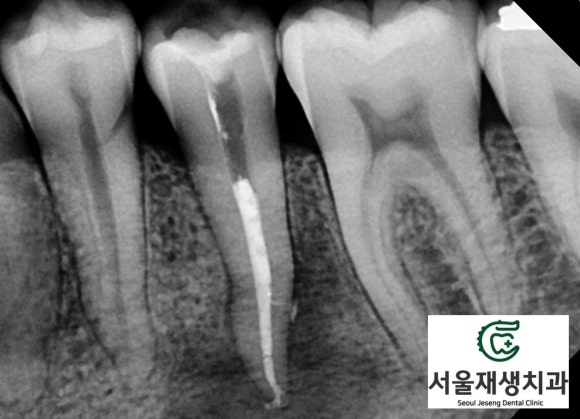

CT의 도움이 필요한 순간!

![[치외치신경치료] 뿌리 끝 염증이 커서 발치해야된대요! 치아 머리에 볼~록! 알고보면 무서운 작은 혹 (서울재생치과) 관련 이미지 13](https://pub-9f2bb3498faf4d1d8714b41df24753e3.r2.dev/content/clinics/archive/nqmm0udu86/naver_blog/honeybeevuvu/assets/by_hash/7982d46f8392fd0a45b45ff83820f0c5cfe012543d06151e9e8c3ed314e6f903.jpg)

U자형의 잇몸뼈 내부가

텅~텅 비어있습니다.

광범위한 염증 때문에

뼈가 모두 녹아버렸군요.

![[치외치신경치료] 뿌리 끝 염증이 커서 발치해야된대요! 치아 머리에 볼~록! 알고보면 무서운 작은 혹 (서울재생치과) 관련 이미지 14](https://pub-9f2bb3498faf4d1d8714b41df24753e3.r2.dev/content/clinics/archive/nqmm0udu86/naver_blog/honeybeevuvu/assets/by_hash/f698ab08a769f77f70e1ab2e4b7243c4a5a755c566e6d8d8e637096050cf8d32.jpg)

내부의 뼈가 다 녹은 것도 모자라

단단한 테두리뼈도 일부 녹이고 있습니다.

그 결과,

잇몸쪽으로 불거져나오는

잇몸염증이 발생하게 되었습니다.

![[치외치신경치료] 뿌리 끝 염증이 커서 발치해야된대요! 치아 머리에 볼~록! 알고보면 무서운 작은 혹 (서울재생치과) 관련 이미지 15](https://pub-9f2bb3498faf4d1d8714b41df24753e3.r2.dev/content/clinics/archive/nqmm0udu86/naver_blog/honeybeevuvu/assets/by_hash/d4e0dece32d30b1b6ab0b453c776a0a04ffa7773279134518fb6282492056c5c.jpg)

더군다나, 염증의 하방에는

턱을 지나가는 가장 큰 신경인

'하치조신경관'이 있어,

언제라도 '감각이상'이 일어날 수 있는

상황이었죠.

조금만 더 늦었어도 큰 일 나실 뻔 했습니다.